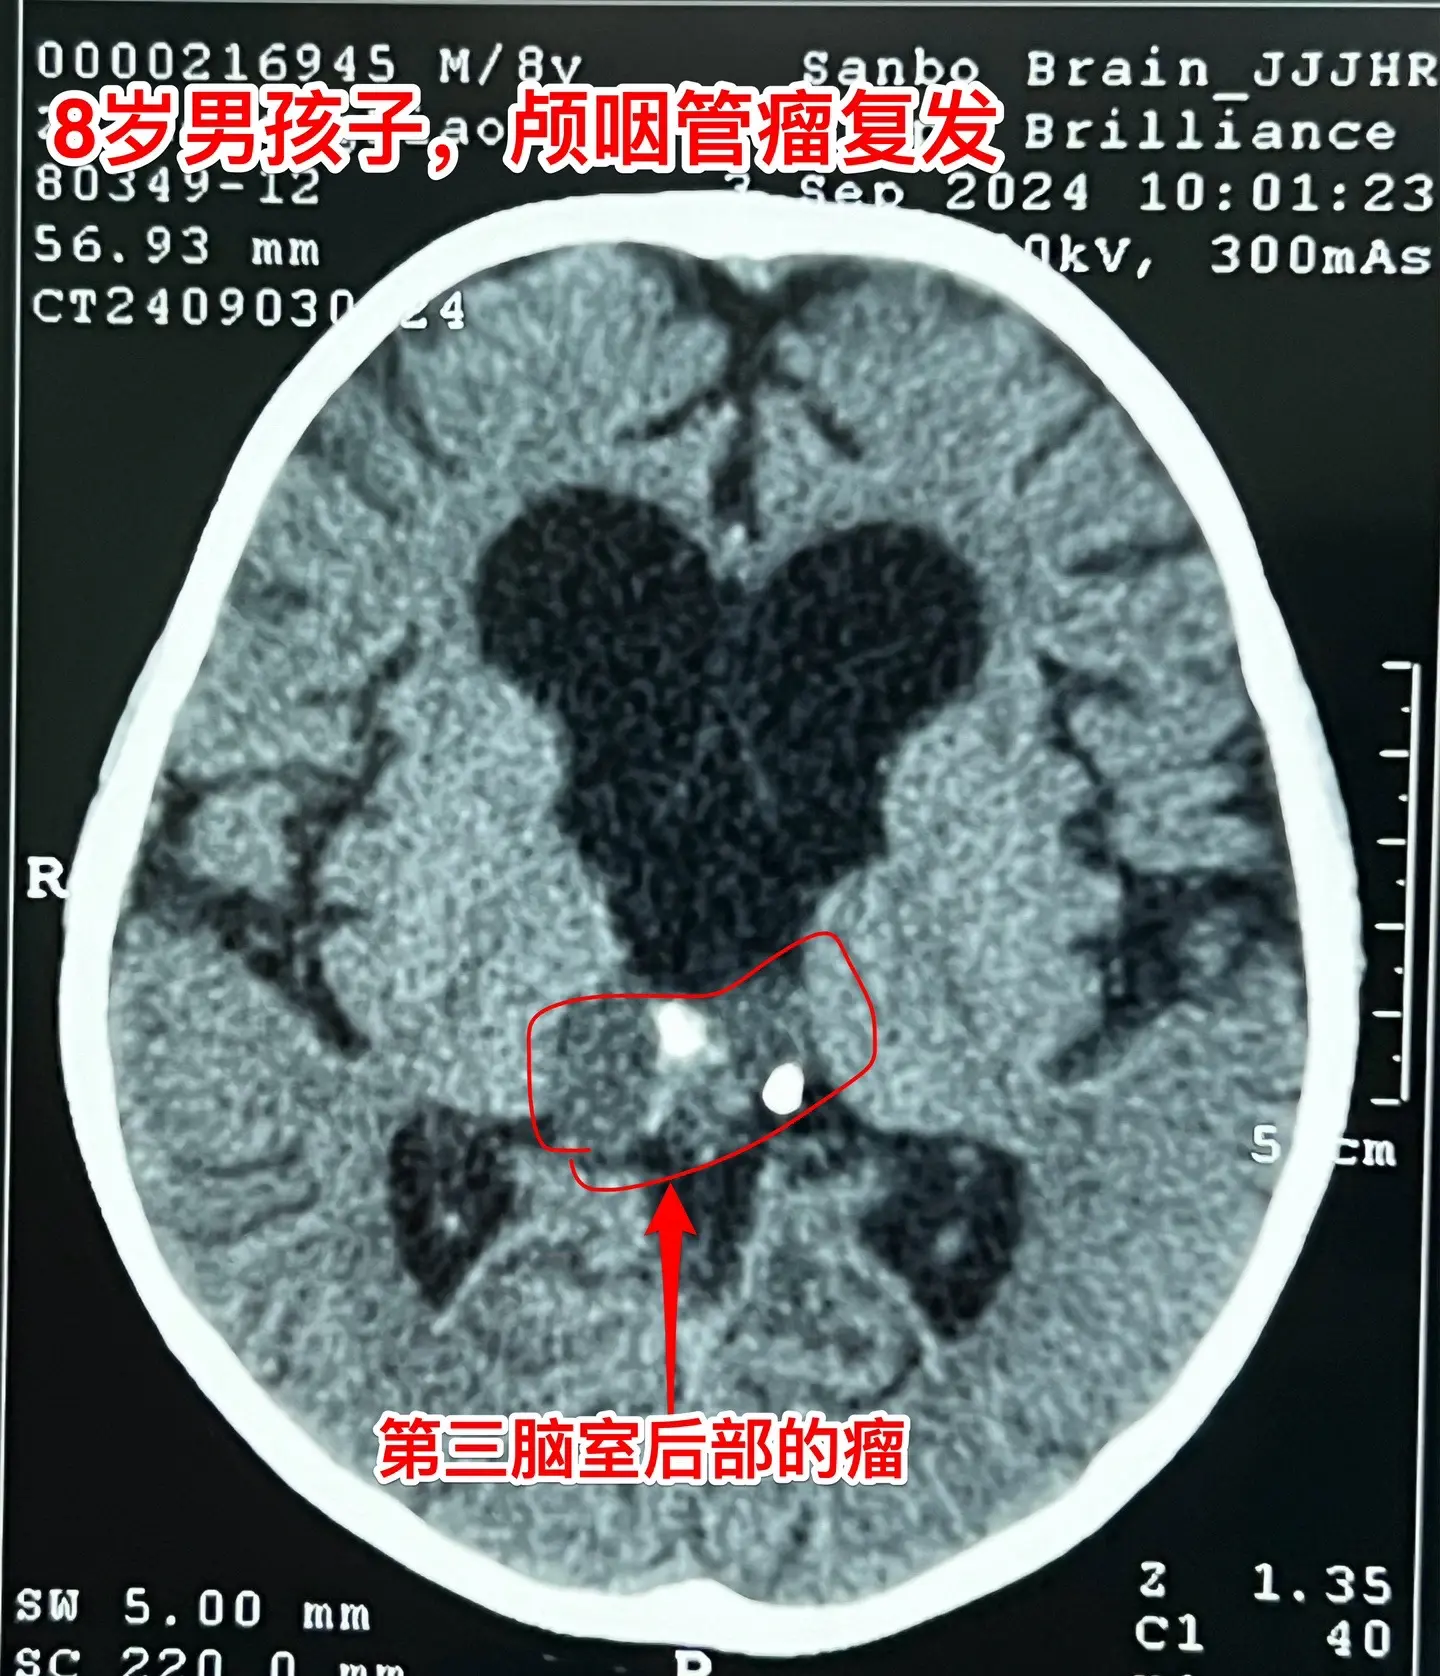

昆明男孩在14个月时间内两次大手术。昆明的8岁男孩子,2023.3在昆明发现颅咽管瘤,体积很大。这样的肿瘤想切干净是很有难度的。2023.7.1在北京市某医院作了经鼻手术,当时告知家长肿瘤得到完全切除。 2024.7复查磁共振显示第三脑室后部肿瘤复发,当时小孩子没有任何症状,找我咨询,我建议先观察。2024.9小孩子出现视物模糊、眼球活动障碍,复查磁共振显示第三脑室后部的肿瘤体积增大了,不得不接受手术治疗。住院后作CT发现肿瘤不单单是在第三脑室后部,鞍区及鞍上均发现散在的钙化。这就提示残留的肿瘤远不止一处。 9.25作了开颅手术,顺利切除所能看见的十来个肿瘤灶。手术后CT显示鞍区及鞍上的小钙化均被切除。我如实告诉家长,后面还不保险,肿瘤仍有复发的可能性,需要定期复查。